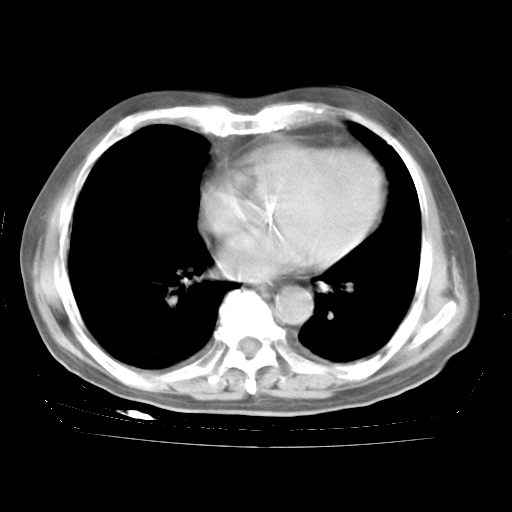

今天部分检查

轻微咳嗽,无痰,(体温正常时)R20次/分,P75次/分,双肺底、腋下可闻及少量捻发音。下肢轻度浮肿。

血常规:白细胞9.11×109/L,N0.92,L5.64,血小板39.2×109/L,HB148g/L,ESR2mm/H。

尿常规:潜血+

血生化:总蛋白69.71g/L,白蛋白38.40g/L,球蛋白31.31g/L,CRP27.9mg/L,尿素氮11.98mmol/L,肌酐106μmol/L,乳酸脱氢酶1099 U/L,肌酸激酶108U/L,CK-MB 61U/L。

腹部B超:胆囊壁增厚,肝、胆、胰、脾、肾无异常,肠系膜淋巴结、腹膜后淋巴结无增大。

ECG:右心室增大

心脏超声检查:无右心室增大。

增加治疗:异烟肼、利福平、乙胺丁醇,静滴左氧氟沙星、参麦注射液。甲强龙从80mg暂减为40mg。

强的松3月1日改为10mg qd,4月1日改为10mg qod。3月份以前的减量过程和环磷酰胺疗程需等明天查看记录(我岳父自己做的记录在他家里)。